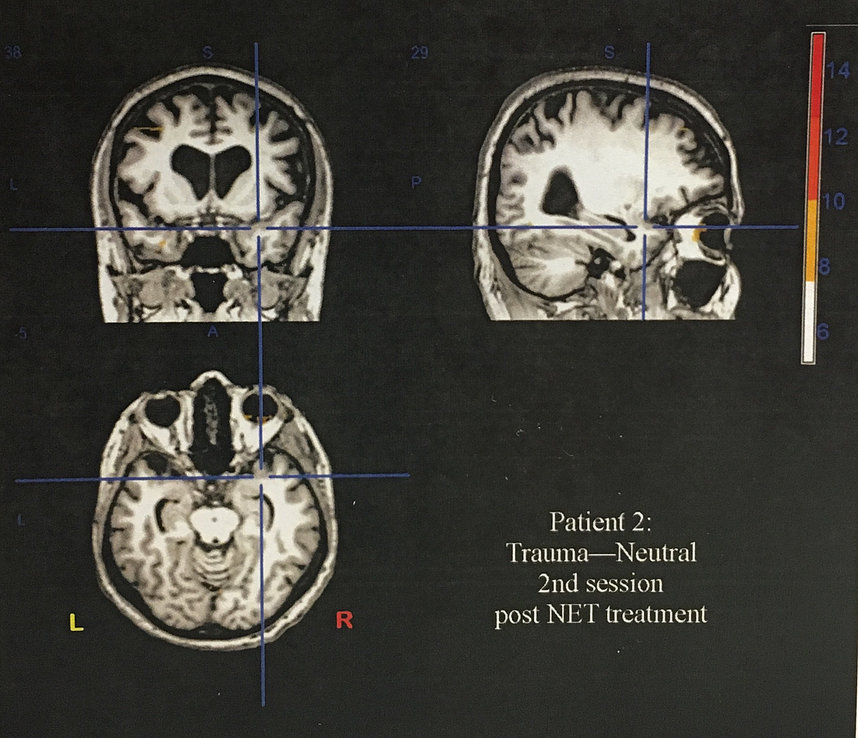

6. Mental and emotional stresses are removed through a technique developed by Dr. Scott Walker known as NET MIND BODY. This simple and effective technique removes the physiology of unresolved mental

emotional traumas. It is interesting to note that a scar will always have a mental or emotional trauma existing with it whether it be from injury or surgery. The images below are functional MRIs of an individual with PTSD, post-traumatic stress disorder. these images were taken at a research study at Thomas Jefferson University in Philadelphia. The simple and elegant technique known as NET was able to eliminate the symptoms of PTSD quickly and without drugs.